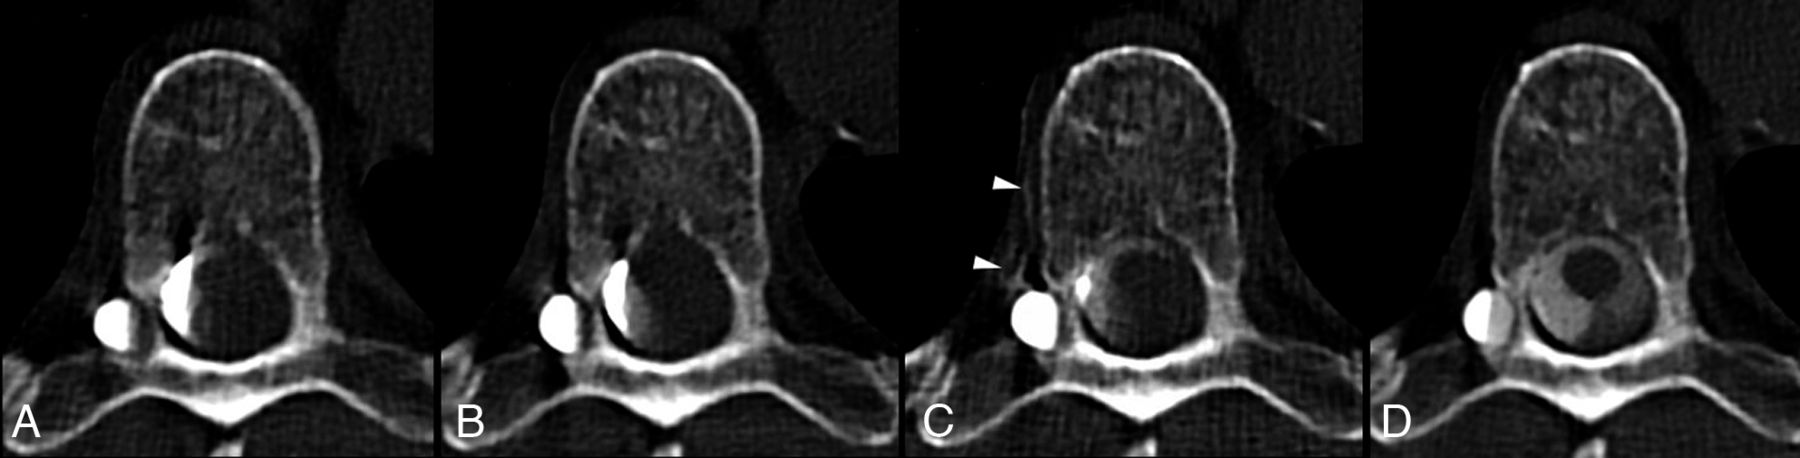

Lateral decubitus dCTM-BT was performed for all patients on 2 consecutive days, typically starting right side down on day 1 and followed by left side down on day 2. Two-day studies were performed, even if a CVF was found on the first day, to ensure a complete evaluation and exclude the possibility of multiple CVFs. The patient was positioned on the CT table in the lateral decubitus Trendelenburg position, with head downward and hips elevated, using angled foam wedges that place the patient at a 10–13° angle (Figure 1A). Pillows were placed under the patient’s head and knees, and the arms were placed at or above the head, keeping the hands together for comfort to minimize motion artifacts. A frontal scout CT image of the patient was then reviewed to confirm Trendelenburg spine angulation at a minimum of 5°, which will allow for the free cephalad flow of intrathecal contrast.5

Lateral decubitus dynamic CT myelogram with real-time contrast bolus tracking (dCTM-BT): A, Frontal CT scout image shows patient in the left lateral decubitus position on the CT gantry table, with the hips placed at the apex of a custom firm foam wedge in the Trendelenburg position, at an angle of approximately 10°, to facilitate the caudocranial flow of contrast from the lumbar puncture towards the cervical spine. B–D, Real-time contrast bolus monitoring axial scans at the level of T5 (A, dashed line) with axial slices taken at 5-second intervals until the visualization of dense contrast (D, arrow). Note that dense contrast visualization is typically observed immediately after the initial appearance of contrast (C, arrow). E, Graph of density (Hounsfield units, HU) of monitored contrast bolus over time (region of interest placed at arrow in panels C and D; note that this graph is for illustrative purposes and is not utilized during the procedure). F, Axial CT myelogram showing the contrast enhancement of the paraspinal veins at the left T10, indicating a CSF-venous fistula (F, arrowheads).

Real-Time Bolus-Tracking and Dynamic/Multiphasic CT Acquisitions.

Bolus-tracking acquisitions are included in our CT software (Somatom Definition Flash; Siemens) and are widely used for contrast bolus monitoring for angiographic CT studies. The bolus-tracking pre-monitoring level was placed at the upper thoracic spine, typically T2 to T5, using the frontal and lateral CT scout images (Figure 1A). The bolus-monitoring intervals were set at 5 seconds per scan with manual triggering of the scan by the proceduralist. The rationale for placement in the upper thoracic spine was that due to the inherent delay from the time of bolus-tracking to the time of CTM acquisition, contrast would be expected to have just reached the cervical spine by the time of the first CTM acquisition. Initial pre-monitoring acquisition (Figure 1B) was performed and reviewed to ensure that the patient was not tilted either forward or backward, and, if needed, subtle patient adjustments were made. With the proceduralist in the room, bolus-tracking monitoring was then initiated, and 10 mL of iodinated contrast (Omnipaque 300) were hand-injected at approximately 1 mL/second. During the injection, the proceduralist inspected the axial bolus-tracking acquisitions in real-time for confluent dense layering intrathecal contrast, which was typically >1500 HU in density and observed on the bolus-tracking scan immediately after the first appearance of contrast (Figure 1C-, D). Once dense contrast was visualized, the proceduralist signaled to the CT technician to trigger the CTM acquisition, which was performed in a cranial-caudal direction to minimize the time to move from the level of the monitoring to the start of the acquisition level. We performed manual triggering for the scan with a qualitative assessment of the dense contrast as subtle patient movement. Often, only approximately 6–7 mL of contrast were injected by the time of the acquisition. In the rare event that contrast was not visualized during the real-time bolus tracking, a saline chase bolus, similar to that performed for DSM, was given to further encourage the cephalad flow of contrast.5 At the time of the CTM acquisition, the proceduralist can either stay in the room or place the syringe setup in a sterile fashion on top of the patient and exit the room to reduce the radiation dose to the proceduralist. Following the initial CTM acquisition, which is typically acquired 15–30 seconds after the visualization of dense contrast on the bolus-tracking and thereby allows for the movement of the CT table, the remainder of the contrast was hand-injected. Additional CTM scans were performed 30–60 seconds (caudal-cranial acquisition direction) and 60–120 seconds (cranial-caudal acquisition direction) after the initial scan. The images were then reviewed for CVF visualization and the complete filling of the diverticulum, as we have anecdotally noted that a subset of CVFs only become visible after the complete filling of the adjacent diverticulum (Figure 2). Based on the diverticulum filling, additional scans were obtained at roughly 1–2 minute intervals. Each CTM acquisition was performed by covering the cervical, thoracic, and lumbar spine to the level of the lumbar puncture, with each acquisition lasting 10–20 seconds on a 128-slice CT scanner (Somatom Definition Flash). Each acquisition was also performed during instructed patient inspiration over 10–20 seconds to increase the conspicuity of the CVF.11 Axial CT reconstruction was performed at a thickness of 0.6 mm, using bone and soft tissue kernels to allow for the detection of subtle CVFs. An example of multiple dynamic images obtained from a dCTM-BT study is shown in Figure 2.